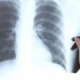

Stručnjaci, kako prenosi Slobodna Dalmacija, podsjećaju da se tuberkuloza ne prenosi poput gripe ili prehlade. Za zarazu je najčešće potreban dugotrajan i blizak kontakt u zatvorenom prostoru. Liječnici naglašavaju da kratkotrajan boravak u trgovini, poput prolaska pored oboljele osobe ili plaćanja na blagajni, predstavlja vrlo nizak rizik.

Tuberkuloza je danas izlječiva bolest, a zdravstveni sustav ima jasno propisane protokole za postupanje u ovakvim situacijama.